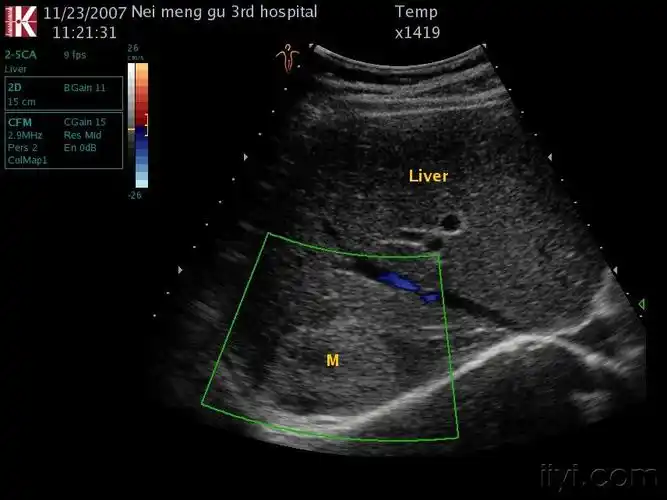

肝血管瘤 - 超声医学讨论版 - 爱爱医医学论坛